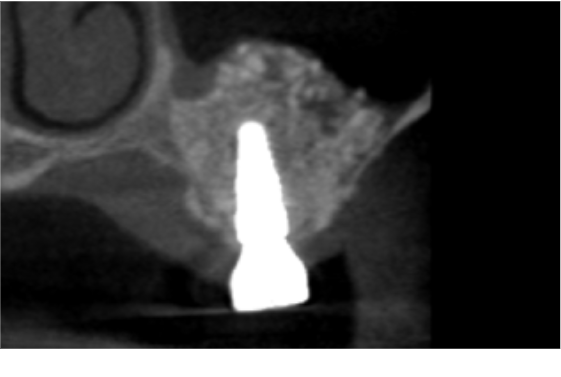

症例2

| 項目 | 詳細 |

|---|---|

| 患者様データ | 70代 女性 |

| 来院時の主訴 | 「歯周病の痛みをとっていただきたい。」 |

| 医院の診断 | 重度歯周病、歯牙欠損 |

| 通院期間 | 6か月 |

| 来院回数 | 5回 |

| 治療費 | 総額:850,000円(税抜) 【内訳】 サイナスリフト350,000円、インプラント埋入手術250,000円×2 |

| リスクと副作用 | 定期的なメンテナンスが必要、術後若干の腫れと痛み |

| ここがこだわりのポイント!☝ | 骨が少なくインプラント埋入ができない所にサイナスリフトを行うことで骨を再生し、インプラント治療が可能になりました! |